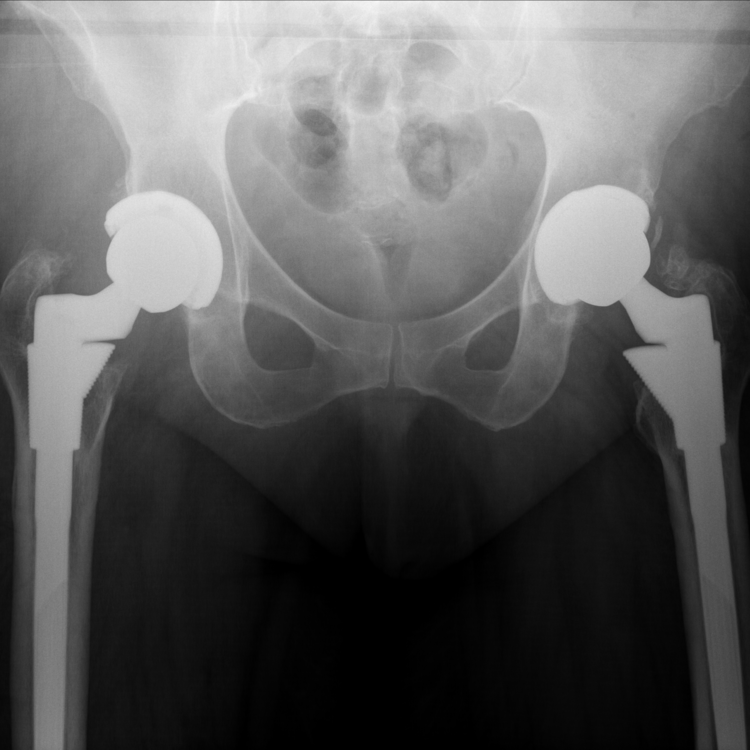

Anteroposterior plain radiograph of the pelvis demonstrates bilateral well fixed and well positioned S-ROM Pinnacle MOM hip replacements. Both cups and stems appear stable and well positioned.

Anteroposterior plain radiograph demonstrating the new liner of the right THR. The head bearing surface is visible on the right side because the right acetabular liner is now made of polyethylene.